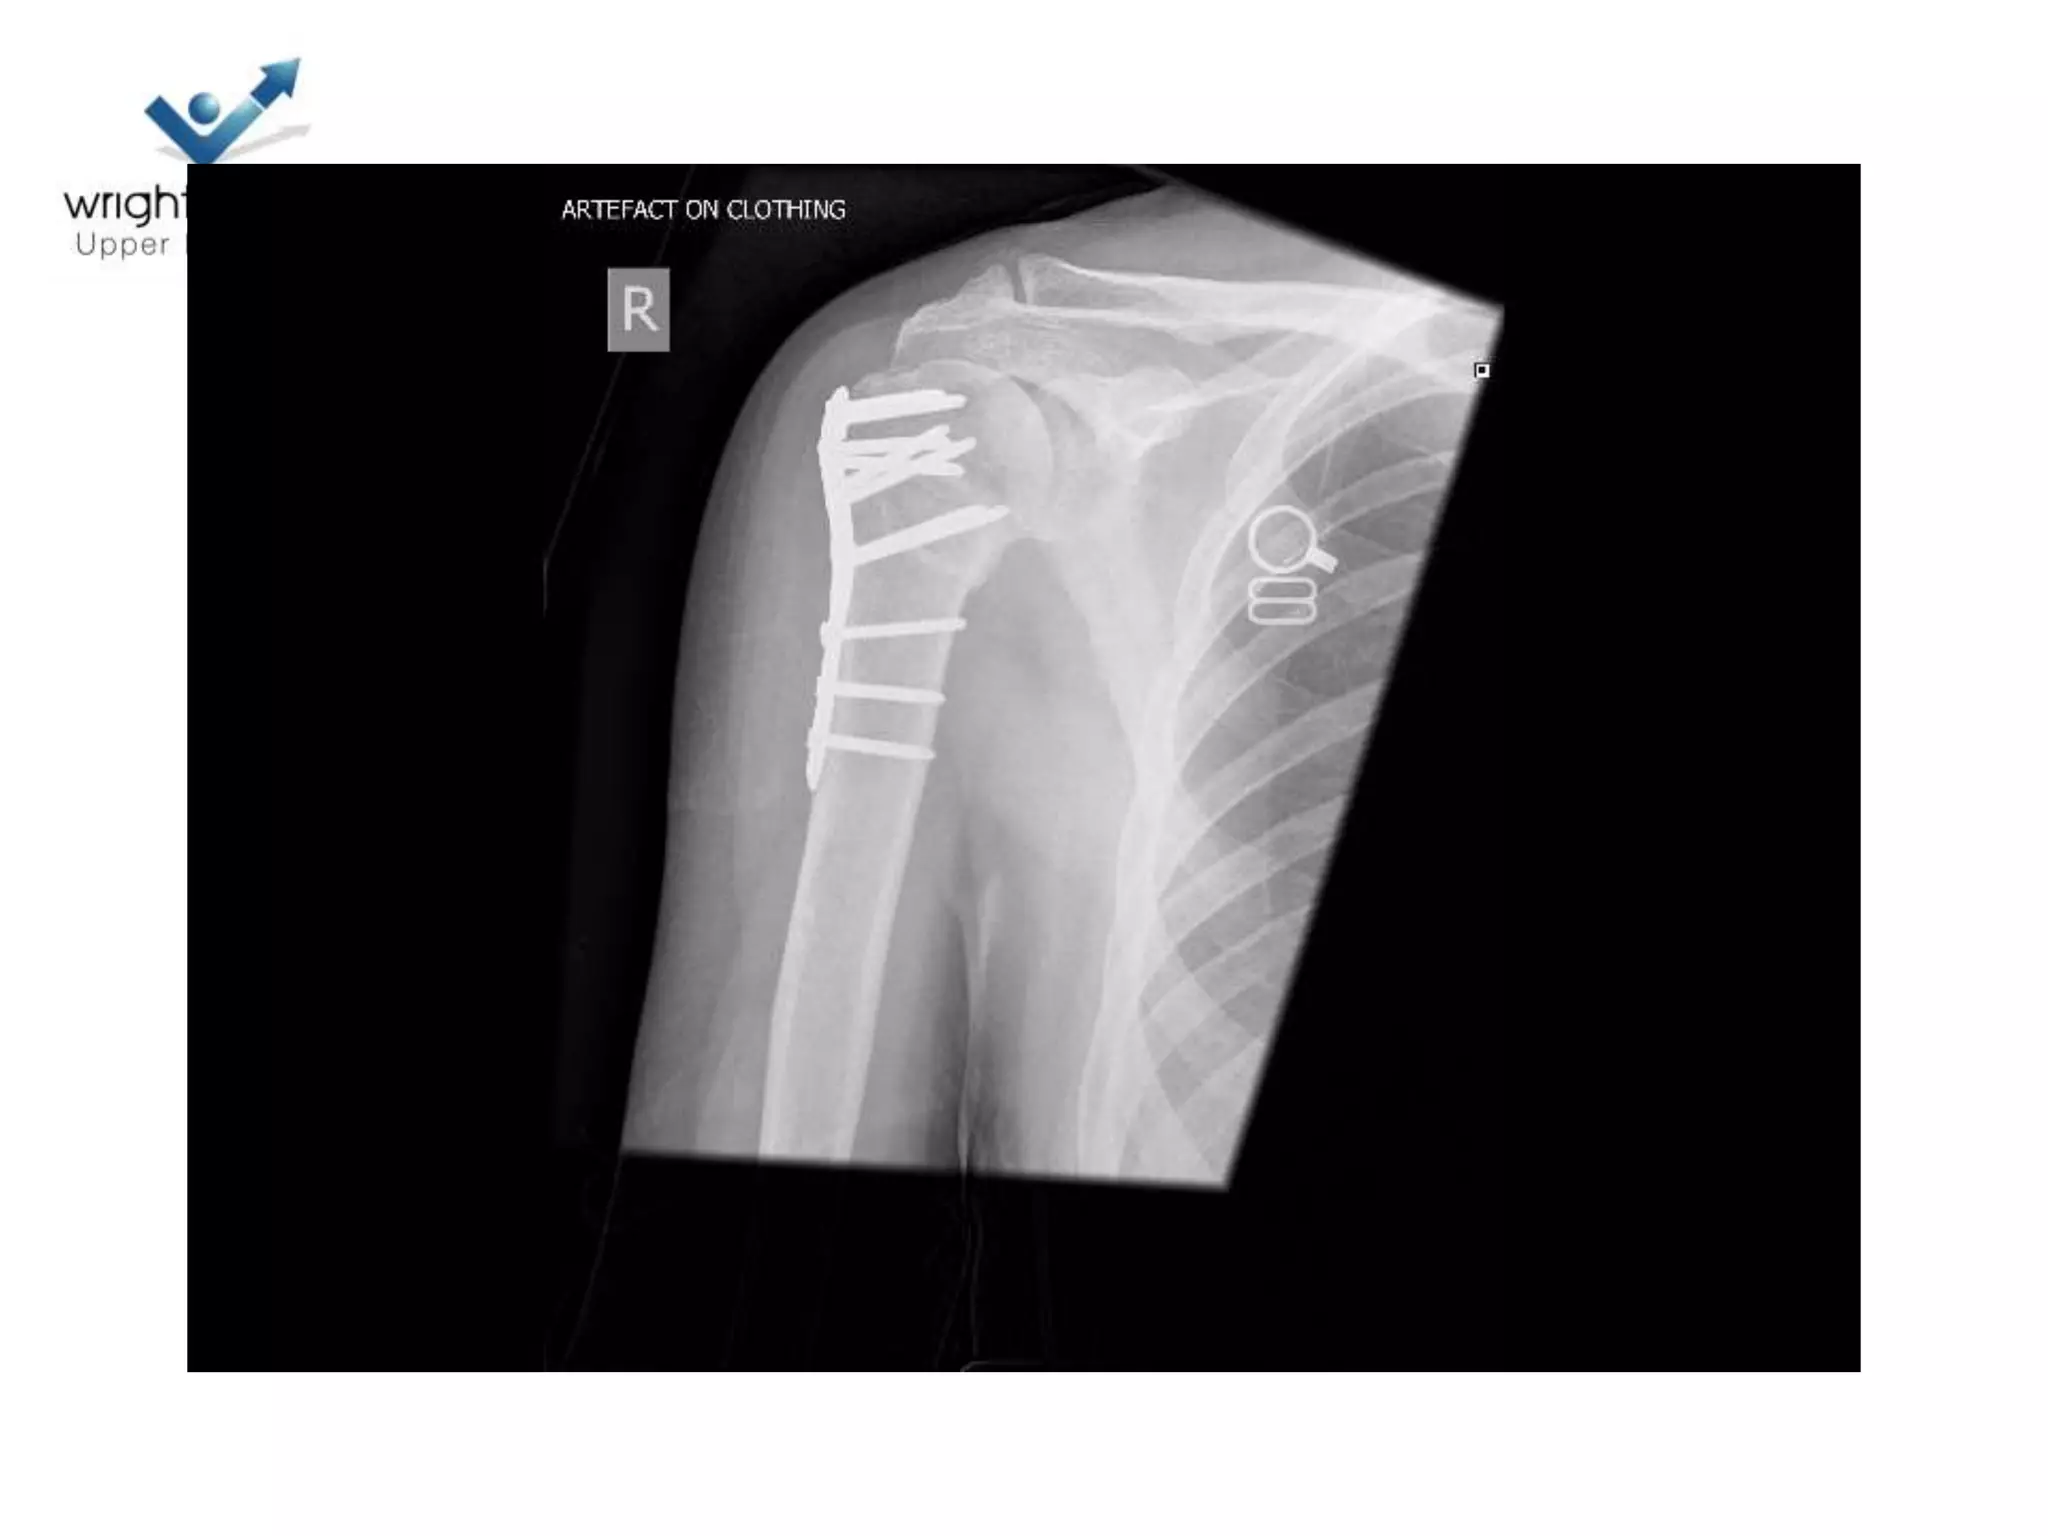

Locking plate; Tips

Locking plates: Tips

Locking plate: Tips

• Belts and braces